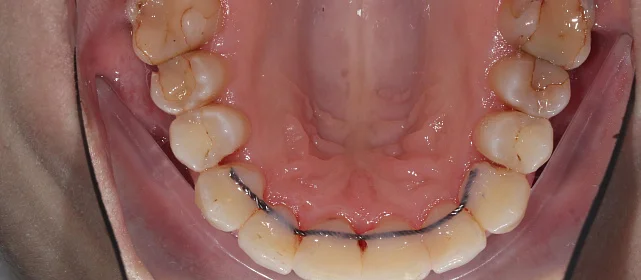

Установка ретейнеров на нижнюю и верхнюю челюсть

Фотографии опубликованы с согласия пациента

Дьячкова Инна Владимировна

Стоматолог - ортодонт

Стаж более 11 лет